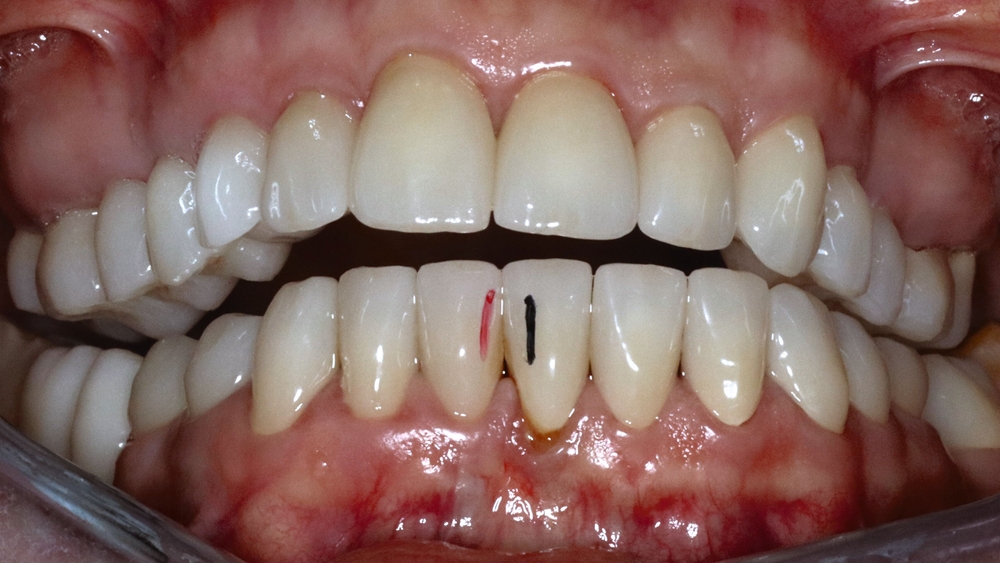

Die Patientin schilderte eine deutliche Instabilität des Zusammenbisses mit punktuellem Kontakt auf der linken und fehlenden Zahnkontakten auf der rechten Seite seit dem Tag der Insertion des Zahnersatzes. Ein annähernd stabiler Zahnkontakt sei nur durch aktiven Verschub des Unterkiefers nach rechts im Sinne eines Eingleitens in die Interkuspidation des Zahnersatzes erreichbar. Bei Provokation dieser „schiefen“ Unterkieferposition komme es jedoch aufgrund der muskulären Anstrengung nach kurzer Zeit zu Beschwerden. Die Patientin gab in diesem Zusammenhang Schmerzen und eine Grundanspannung der Kau-/Nackenmuskulatur und Kopfschmerzen an, jeweils links > rechts (Abbildung 4).

Die Sprechfunktion und die Funktion der mimischen Muskulatur (zum Beispiel Küssen) beschrieb sie als anstrengend und ermüdend. Die Kieferöffnung verlaufe schräg nach links und sei schmerzhaft eingeschränkt. Aufgrund der instabilen Zahnkontakte sei die Kaufunktion deutlich limitiert und beschwerlich. Im Bereich der linken Vorkontakte komme es wiederholt zu Einbissverletzungen und mechanischen Irritationen der Wangeninnenseite. Ebenso wurden Schmerzen im Zungenbereich links und zeitweise Empfindungen von Taubheitsgefühl beschrieben. Als ein weiteres Problem nannte die Patientin, dass der linksseitige Vorkontakt der Kronen dauerhaft bestehe und ein Nichtkontakt im Sinne einer Ruhelage nur durch kontinuierliche aktive Kieferöffnung möglich sei.

Mobilität des Unterkiefers eingeschränkt: Kieferöffnung aktiv ohne Schmerz 20 mm, aktiv mit myogenem Schmerz 32 mm, passiv 42 mm (Deflexion nach links, myogener Schmerz); unterdurchschnittliche Rechtslaterotrusion 4 mm und Linkslaterotrusion 6 mm (jeweils myogen schmerzhaft); Protrusion 4 mm (myogen schmerzhaft); Vertikaldimension unphysiologisch zu hoch (circa 2–3 mm) (Abbildungen 5 und 6).

Statische Vorkontakte 25/34 und 26/35 in geführter zentrischer Kondylenposition (entspricht dem subjektiven Erstkontakt) (Abbildungen 7 und 8) mit forcierbarem Gleiten in die maximale (Kronen)Interkuspidation circa 3 mm nach rechts (Abbildung 9).